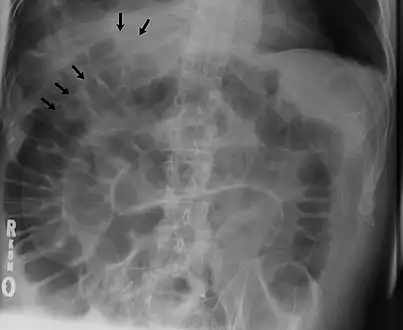

The double wall sign marks the presence of air on both sides of the intestine.[19] However, a false double wall sign can result from two loops of bowel being in contact with one another.[20] The sign is named after Leo George Rigler.[21] It is not the same as Rigler's triad.

Double wall sign. This is a secondary sign of pneumoperitoneum. Patient is supine, and air within the abdomen and lumen of the bowel accentuate both sides of the bowel wall.- Ultrasound finding of pneumoperitoneum known as "peritoneal stripe sign"[24]